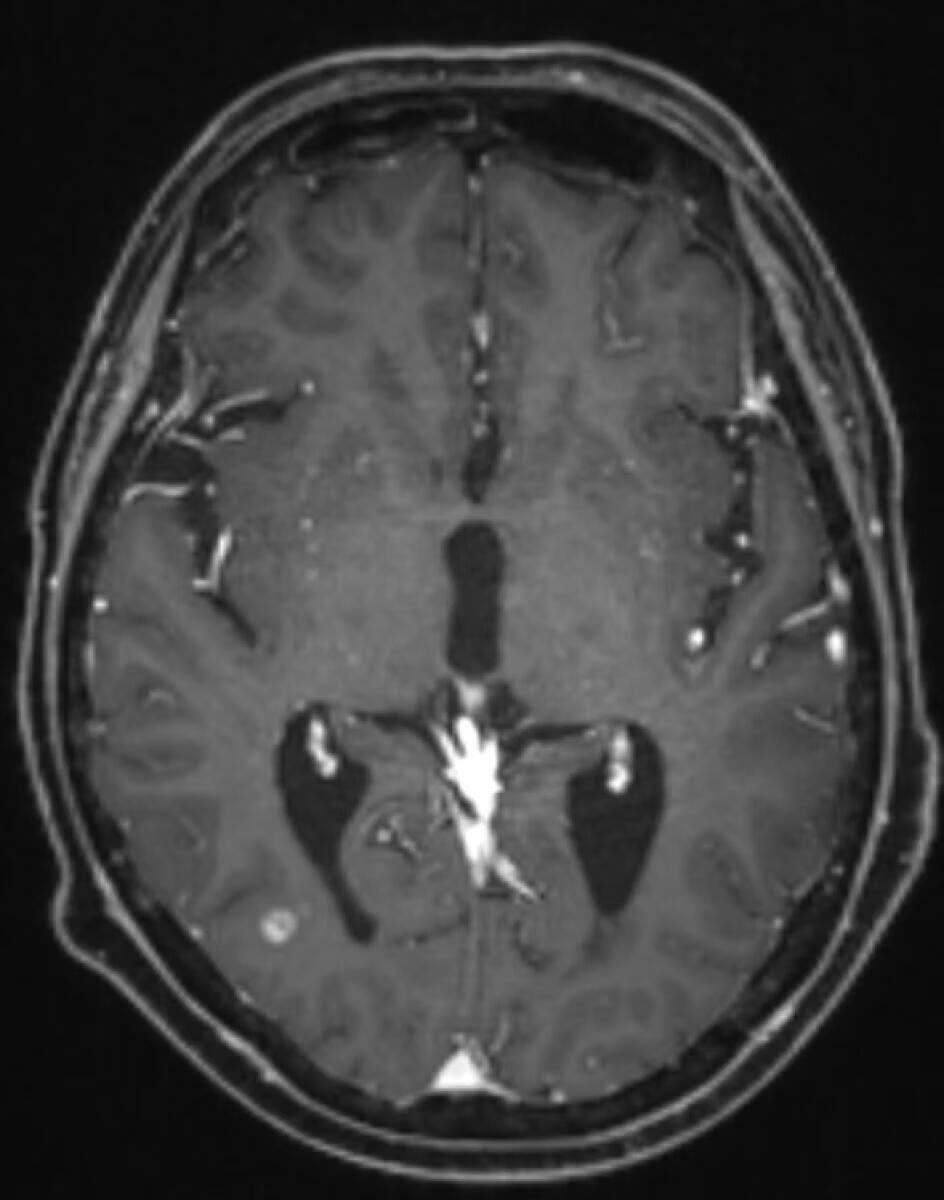

肺腺伴脑转移,放化疗后一直单线奥西,12月初复查头颅新增病灶较前增大,考虑有脑膜转移,目前偶尔头晕,头痛,持续时间短(自确诊以来偶尔都有),本地医生建议双倍奥西,现已经口服双倍20多天,请问没有症状的脑膜转移需要鞘注吗?脑膜转移可逆吗?有没有可能双倍奥西后脑膜转移就消失,病灶缩小了?求各位大佬指导